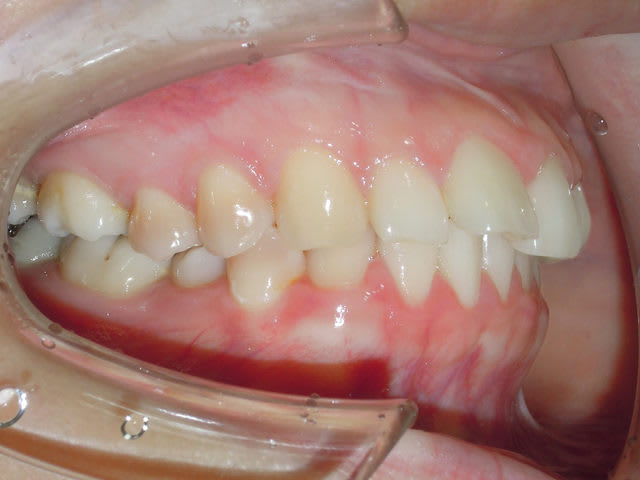

Simple regarder la pano intial il y a le condyle droit qui est dans une position trop antérieur.

Cette patient en fait ne mâcher que du coté gauche, avec le temps une occlusion stable c'est developé mais avec une position asymétrique des condyles.

Vue que cette situation c'était developé sur le long terme la patiente c'était habitué a positionné la mandibule en avant.

Pendant l'examen initial comme un gros débutant de base je me suis focalisé sur l'occlusion et n'est pas fait attention qu'il y avait un décalage entre RC et ICM.

Comme j'était vraiment une buse je n'ais pas fait attention a la pano non plus ( vue que dans 95% des cas il n'y a pas de problème ).

Résultat des course pendant la phase de levelling, déprogrammation neuro musculaire, la patient ne retrouve plus se position d'occlusion non naturelle de maniére simple, donc elle retourne naturellement dans la position la plus confortable pour c'est deux condyle la RC.

Ce qui se traduit pour le jeunot comme une retrusion de la mandibule (qui est en faite une correction de la protrusion initiale) avec prématurité sur les 7, open bite et donc mécaniquement overjet excessif.

Mais si elle fait une protrusion de la mandibule elle retrouve plus ou moins la position initiale.